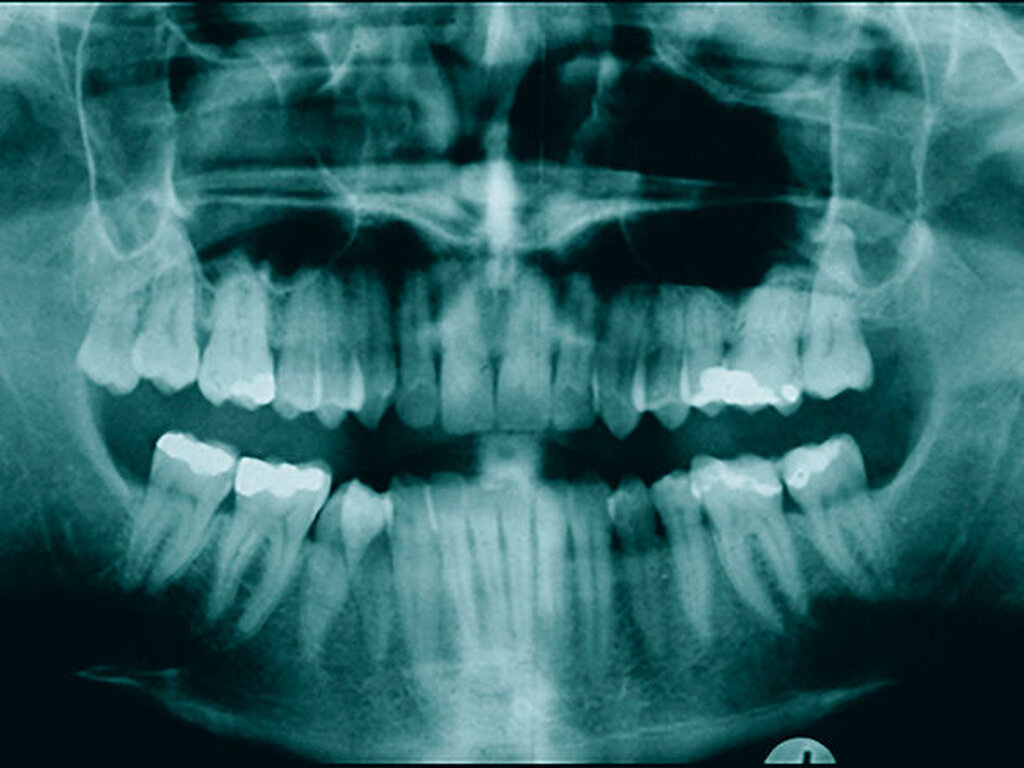

In der Zahnmedizin steht die oben beschriebene Homöopathie zwar nicht im Fokus, deren Weltbild kann aber als eine Art Einstieg in die alternativmedizinische Szene dienen. Sie kann dazu beitragen, sich weiteren alternativmedizinischen Modellen zu nähern, die ihrerseits für die Mundgesundheit gefährlich werden können, wenn sie beispielsweise zu drastischen invasiven Eingriffen mit irreversiblen Schäden motivieren. So gibt es Behandler, die auf der Grundlage sogenannter bioenergetischer Testmethoden (beispielsweise Muskeltests mit „Applied Kinesiology“) invasive Eingriffe wie Entfernungen intakter zahnärztlicher Versorgungen oder Zahnextraktionen (zuweilen sogar Serienextraktionen) vornehmen, unabhängig davon, ob die Versorgungen beziehungsweise Zähne nach aktuellem wissenschaftlichem Erkenntnisstand erhaltungswürdig sind oder nicht. Zahnärzte fräsen im Anschluss an Zahnextraktionen die Kieferknochen zur Beseitigung von vermeintlichen „Störfeldern“ aus und richten dabei erhebliche Schäden an (Abbildung 1).